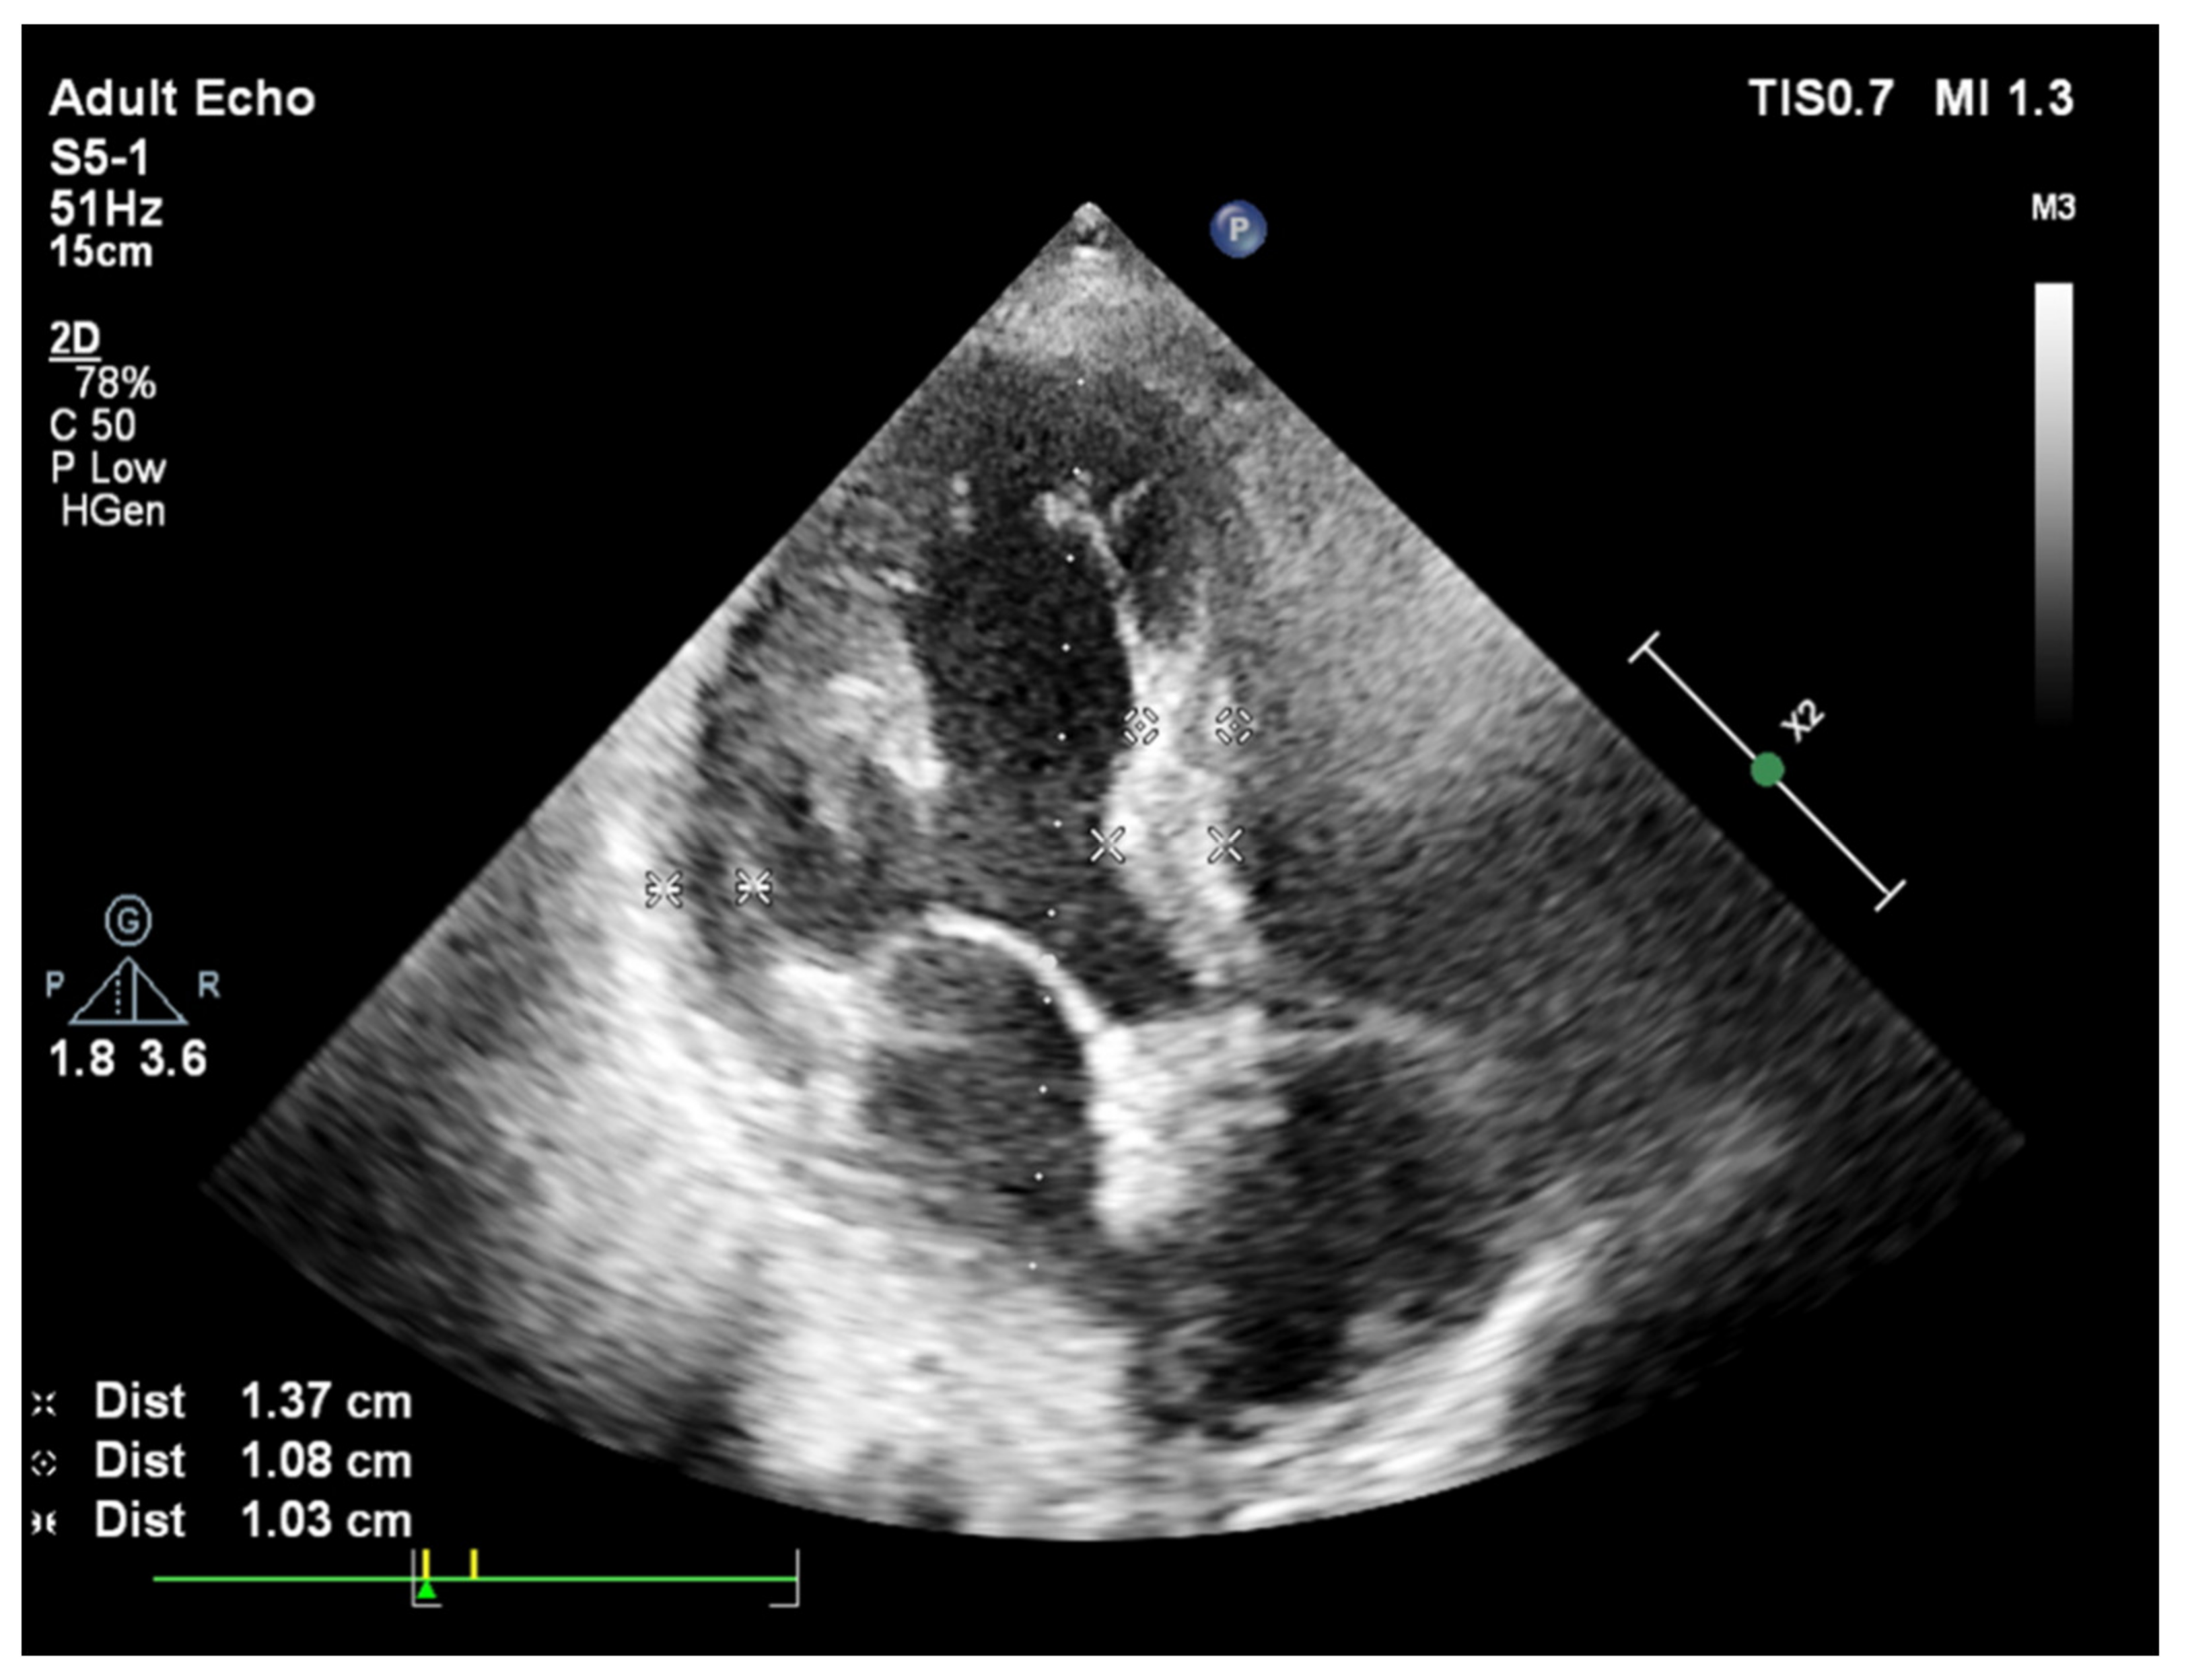

2. Basal Septal Hypertrophy and Clinic Observations

- Yalçin, F.; Topaloglu, C.; Kucukler, N.; Ofgeli, M.; Abraham, T.P. Could early septal involvement in the remodeling process be related to the advance hypertensive heart disease? Int. J. Cardiol. Heart Vasc. 2015, 7, 241–245. [Google Scholar] [CrossRef] [PubMed][Green Version]